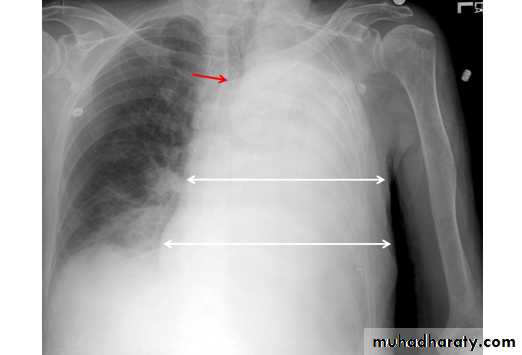

Left upper lobe collapse has distinctive features but can be challenging to identify on chest radiographs by the uninitiated.

Radiographic features

The left upper lobe collapses anteriorly becoming a thin sheet of tissue apposed to the anterior chest wall, and appears as a hazy or veiling opacity extending out from the hilum and fading out inferiorly . It thus reverses the normal slight increase in radiographic density seen as you move down the lung (due to increased thickness of the chest soft tissues).

Parts of the normal cardiomediastinal contour may also be obliterated where the left upper lobe, particularly the lingula abut the left heart border. The anterior parts of the aortic arch are also often obliterated from view.

In some cases the hyperexpanded superior segment of the left lower lobe insinuates itself between the left upper lobe and the superior mediastinum, sharply silhouetting the aortic arch and resulting in a lucency medially. This is known as the luftsichel sign.

The left hilum is also drawn upwards, resulting in an almost horizontal course of the left main bronchus and vertical course of the left lower lobe bronchus.

Non-specific signs indicating left sided atelectasis will also be present, including:

elevation of the hemidiaphragm

'peaked' or 'tented' hemidiaphragm: juxtaphrenic peak sign

crowding of the left sided ribs

shift of the mediastinum to the left

On lateral projections the left lower lobe is hyperexpanded and the oblique fissure displaced anteriorly. There is associated increase in the retrosternal opacity.